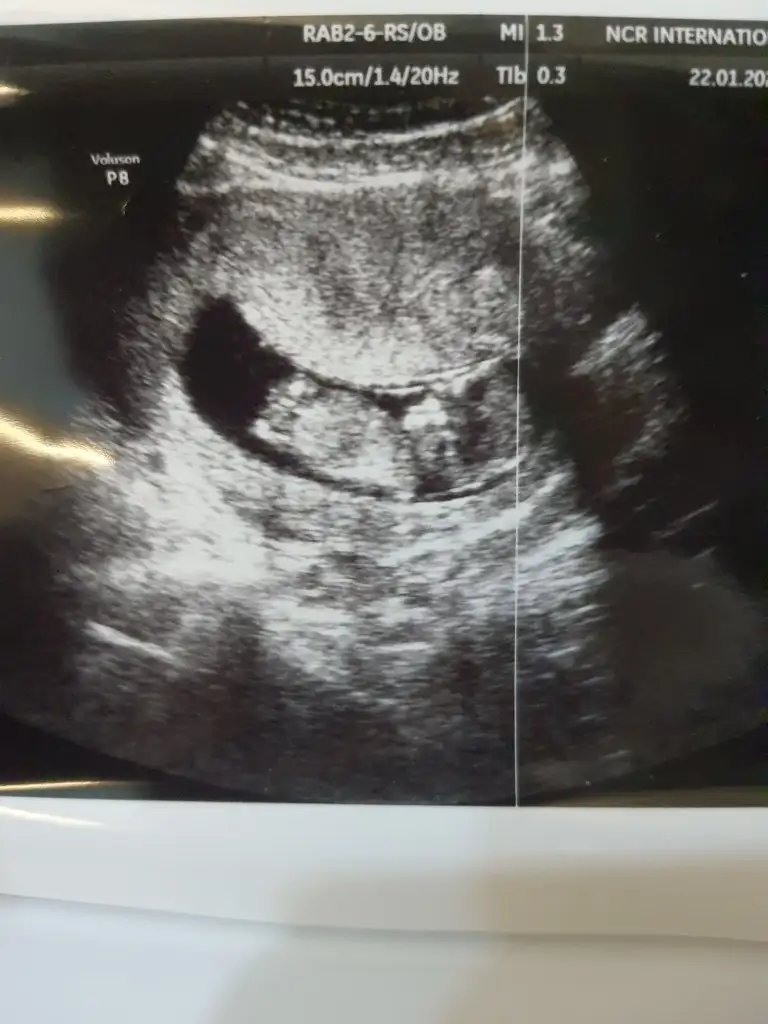

Ikra meyra Ikra meyra canim meraba 12+1 doktorum %80 tahminde bulundu ama sana da sormak istedim bi bakarmisin şimdiden tsk ederim 😇🥰

16114342874286929225332790290193.webp

16114343337338551547173301726829.webp